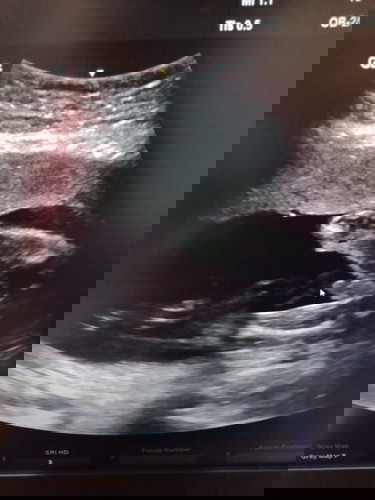

จากที่เคยบอกว่าแม่เลือดจาง (รอผลพ่อ) เมื่อต้นเดือนได้ไปตรวจทั้งพ่อและแม่ วันนี้ผลมาแล้วจร้า พ่อกับแม่ สรุปเป็นพาหะ ทั้งคู่ แต่เป็นคนละสายพันธ์ุ ทำให้ไม่มีผลต่อลูก สบายใจไปอีกเปาะค่ะ แต่ก็ต้องทานยา อย่างสม่ำเสมอ เพื่อหนูนะลูก